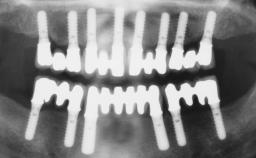

Conventional Loading of Six Implants in the Mandible and Final Restoration with a Full-Arch Metal-Ceramic FDP

A 68-year-old, completely edentulous male patient presented for evaluation and treatment options. He reported excellent general health and was taking no regular medication. He had been edentulous for approximately 12 years, having lost his teeth to periodontal disease and dental caries. The patient’s chief complaint was incompetent function. His secondary concerns included his appearance and the desire for a predictable outcome. He attributed his reduced functional capacity to his lower complete denture, which he described as poor. He was particularly concerned with the denture’s instability and poor fit. In general terms, he was satisfied with the maxillary complete prosthesis. The maxillary prosthesis was characterized by adequate retention, stability, and support, although the fit was considered less than ideal.

# of Implants 6

Defining Characteristics Fully edentulous lower jaw to be rehabilitated with two or more implants

Modality > 4 implants, extending to mental nerve region